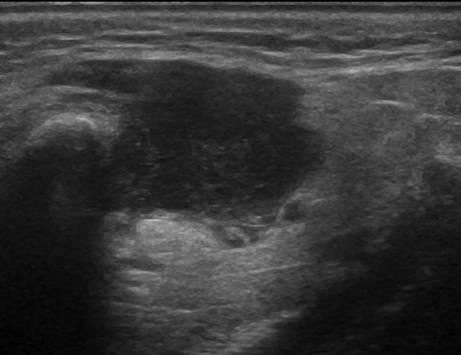

U tuyến nước bọt

» Thông tin: Nam giới – 63 tuổi.

» Lâm sàng: Khối vùng góc hàm.

# Lymphoma tuyến nước bọt dưới hàm.